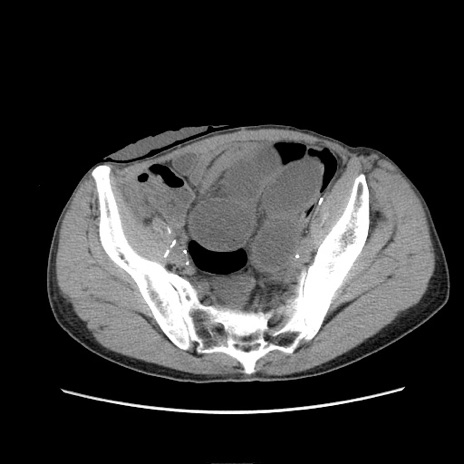

症例11(横断像)

【症例】 60歳代男性

【主訴】 下腹部痛

【現病歴】 本日夜中より下腹部痛の症状認め、受診。

【既往歴】 膀胱癌(膀胱全摘+尿管皮膚瘻術) 、胃癌術後

【身体所見】 BT 35.3℃、PR 58/min、BP 136/98mHg、腹部平坦、軟、腸蠕動音±、ストマ留置あり、左上腹部~正中部に圧痛あり、反跳痛なし。

【データ】WBC 5100、CRP0.01